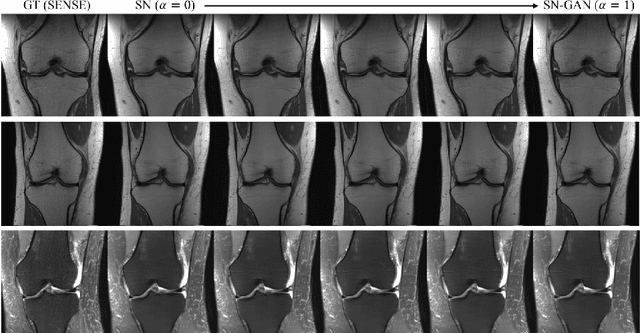

We present a deep network interpolation strategy for accelerated parallel MR image reconstruction. In particular, we examine the network interpolation in parameter space between a source model that is formulated in an unrolled scheme with L1 and SSIM losses and its counterpart that is trained with an adversarial loss. We show that by interpolating between the two different models of the same network structure, the new interpolated network can model a trade-off between perceptual quality and fidelity.